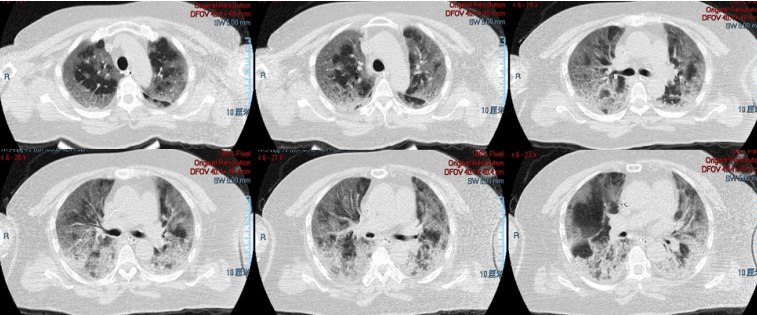

我院收治了一例58岁女性患者,有高血压、慢性支气管炎病史,以发热伴咳嗽9天,加重2天为主诉,2022年12月19日入ICU(D9)。12月13日新冠抗原(+)、12月17日新冠核酸(+),入院后给予经口气管插管及机械通气。PEEP 12 cmH2O,FiO2 1.0,同时联合俯卧位通气。血气分析:pH 7.396,PaCO2 38.5 mmHg,PaO2 68.9 mmHg。后出现循环恶化,予以去甲肾上腺素维持血压。

入ICU前胸部CT比较重,病情进展迅速,入ICU后行气管插管,进行了1周抗炎治疗:甲强龙40 mg qd,第2天加用巴瑞替尼4 mg qd。同时由于患者核酸CT值较低,加用了Paxlovid抗病毒治疗。1周后,患者体温、WBC、PCT、CRP等均下降,但复查胸部CT发现病情较前明显加重。

图片

患者第一份胸部CT(12月18日,D8

用药情况及炎症指标变化

患者第二份胸部CT(12月26日,D16

患者的炎症指标好转,但最能反映病变严重程度的影像反而加重,而且这种影像特点无法用继发感染(细菌/真菌感染)解释。为什么病情(影像及氧合)会加重?我们分析认为问题可能在于抗炎治疗,包括抗炎治疗时机、抗炎治疗药物选择及剂量。